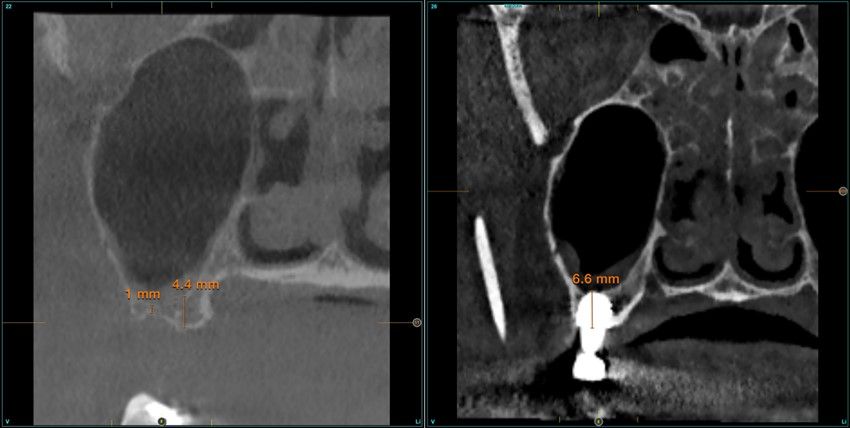

Resultados. Fueron reclutados 13 pacientes en los que se insertaron 30 implantes. Una vez insertados y cargados los implantes, la altura media final fue de 9,68 mm (+/- 2,66), lo que supone una ganancia promedio de 5 mm. A los 10 años, se observó una disminución media de la altura ósea ganada en los implantes en conjunto de 0, 29 mm (+/- 0,77). La media de la pérdida ósea mesial fue de 0,73 mm (+/- 0,75 mm) y la media de la pérdida ósea distal fue de 0,98 mm (+/- 1,2 mm). La supervivencia fue del 100%.

Results.Thirteen patients were recruited and 30 implants were inserted. Once the implants were inserted and loaded, the mean final height was 9.68 mm (+/- 2.66), which represents an average gain of 5 mm. At 10 years, there was a mean decrease in the overall bone height gain of the implants of 0.29 mm (+/- 0.77). The mean mesial bone loss was 0.73 mm (+/- 0.75 mm) and the mean distal bone loss was 0.98 mm (+/- 1.2 mm). Survival was 100%.

Nuestro grupo de estudio modifica esta técnica de elevación transcrestal utilizando para el acceso unas fresas de corte frontal que permiten eliminar la cortical inferior del seno con lentitud sin dañar la membrana de Schneider, eliminándose los osteotomos y el malestar que genera su accionamiento mediante el martillo6-7. Inicialmente el procedimiento fue concebido para ser empleado con material de injerto al igual que el abordaje convencional, pero posteriormente se presentaron variaciones del procedimiento donde se insertaban los implantes sin injerto, utilizándose el propio implante como mantenedor de espacio entre la membrana de Schneider y la cavidad creada entre la membrana y la cresta, permitiendo que esta cavidad no se colapsase y posteriormente fuera colonizada por nuevo hueso7-11.

Los senos tratados con la técnica de elevación transcrestal sin material de relleno muestran un incremento de entre 2,5 mm12,13 hasta 4.4 mm14,15 en la altura ósea lograda sobre el ápice y una supervivencia de los implantes que se sitúa entre un 94 y un 100%16-17. En este trabajo se presenta un estudio retrospectivo donde se ha evaluado la inserción de implantes extracortos (5,5 y 6,5 mm) en zonas posteriores maxilares mediante la técnica de elevación de seno transcrestal con la fresa de ataque frontal sin la utilización de material de injerto, con un tiempo de seguimiento de 10 años para poder objetivar el comportamiento de los implantes a largo plazo y de la técnica empleada.